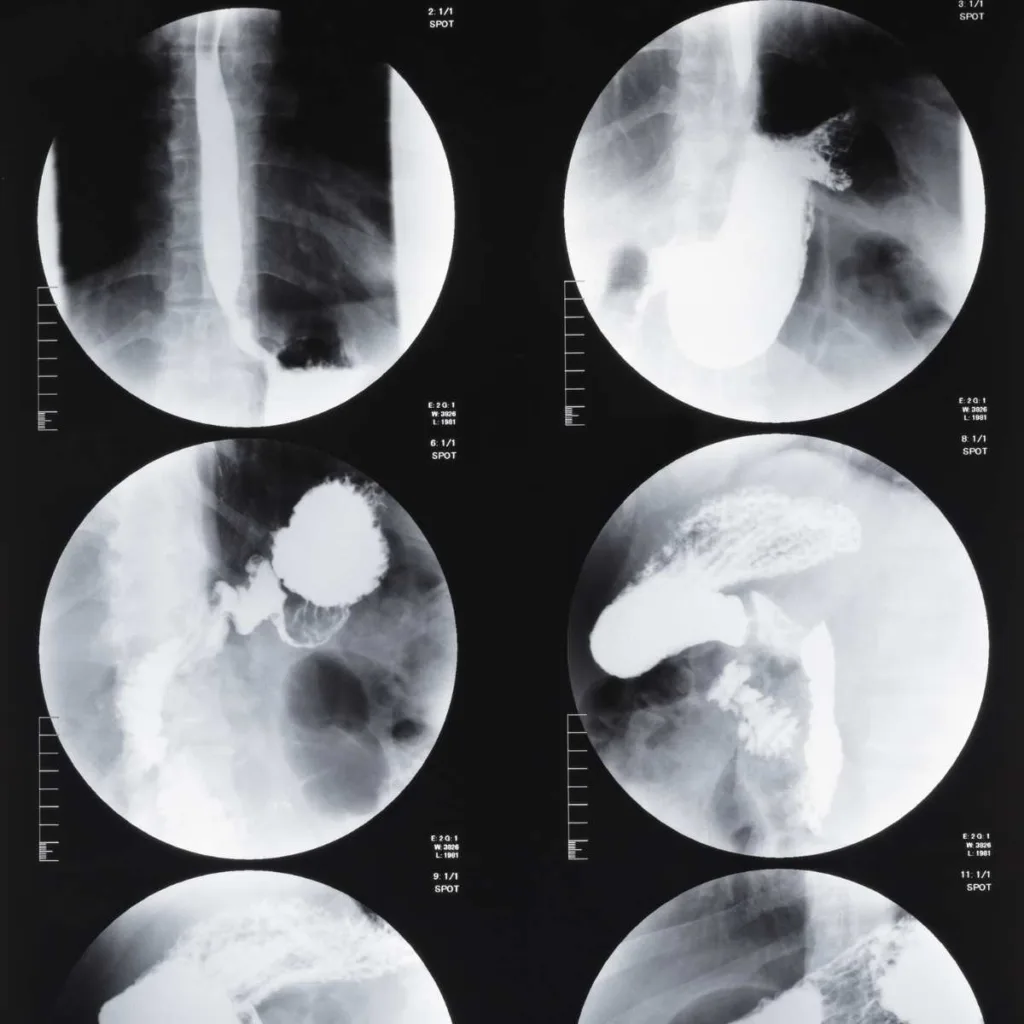

Resonancia Magnética de Tórax